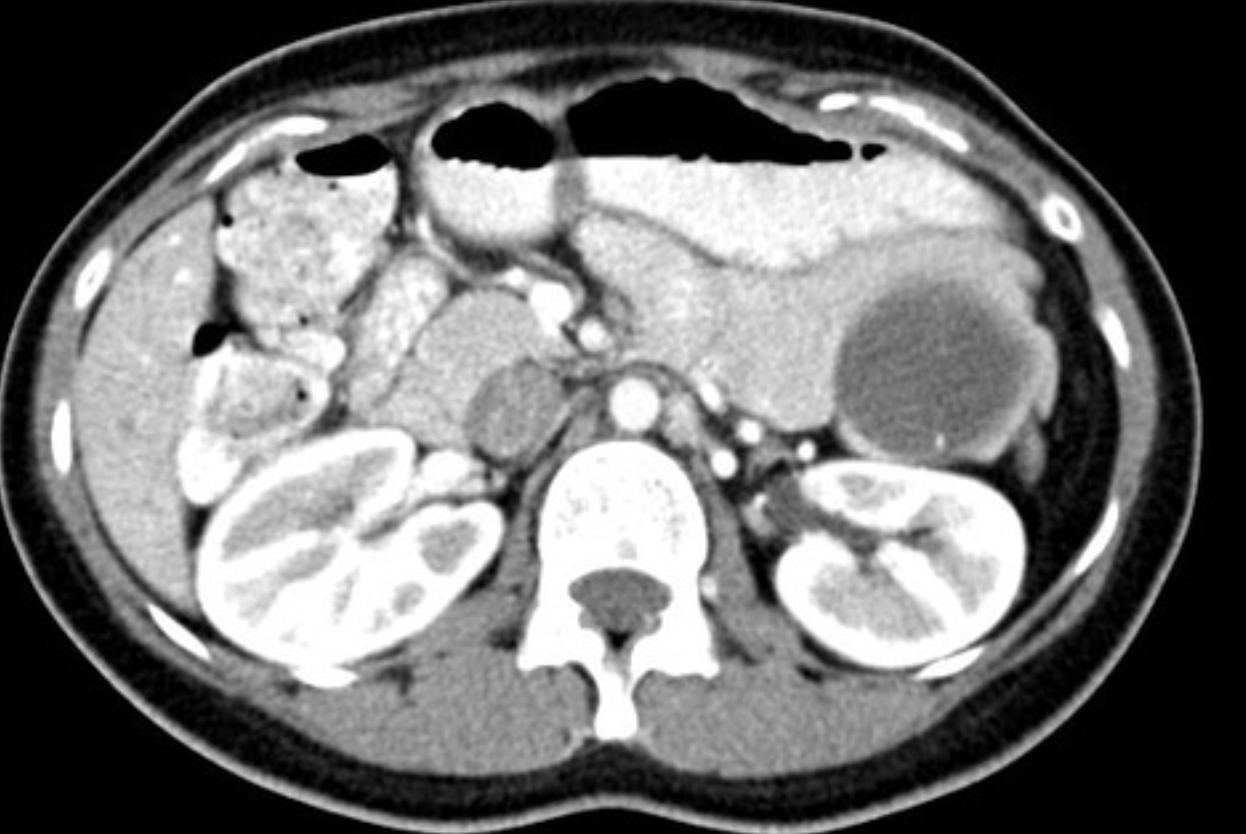

Case Discussion

Ultrasound-guided biopsy of the spleen was performed leading to the rare diagnosis of pancreas acinar cell carcinoma.

Pancreas acinar cell carcinoma highlights:

very rare <1%

exocrine tumour

larger size at diagnosis and often better prognosis than adenocarcinoma

some have paraneoplastic syndrome with hypersecretion of lipase (as in this case), which can lead to fat necrosis of subcutaneous nodules and polyarthralgia

On physical exam, this patient did have subcutaneous nodules in the lower extremities which would be clinically consistent with fat necrosis related to hyperlipasaemia.